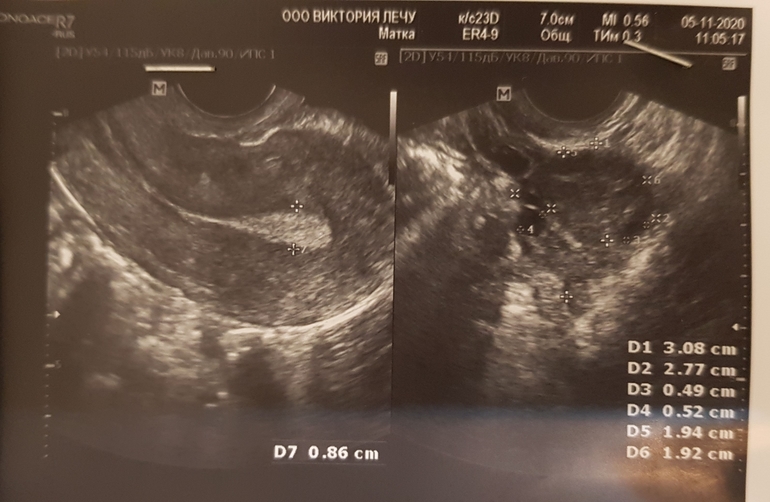

И кстати я была на узи, результаты не очень. Жт 17мм, а эндик 8,6 на 7 дпо.

Структура - на фото белое пятно 😂